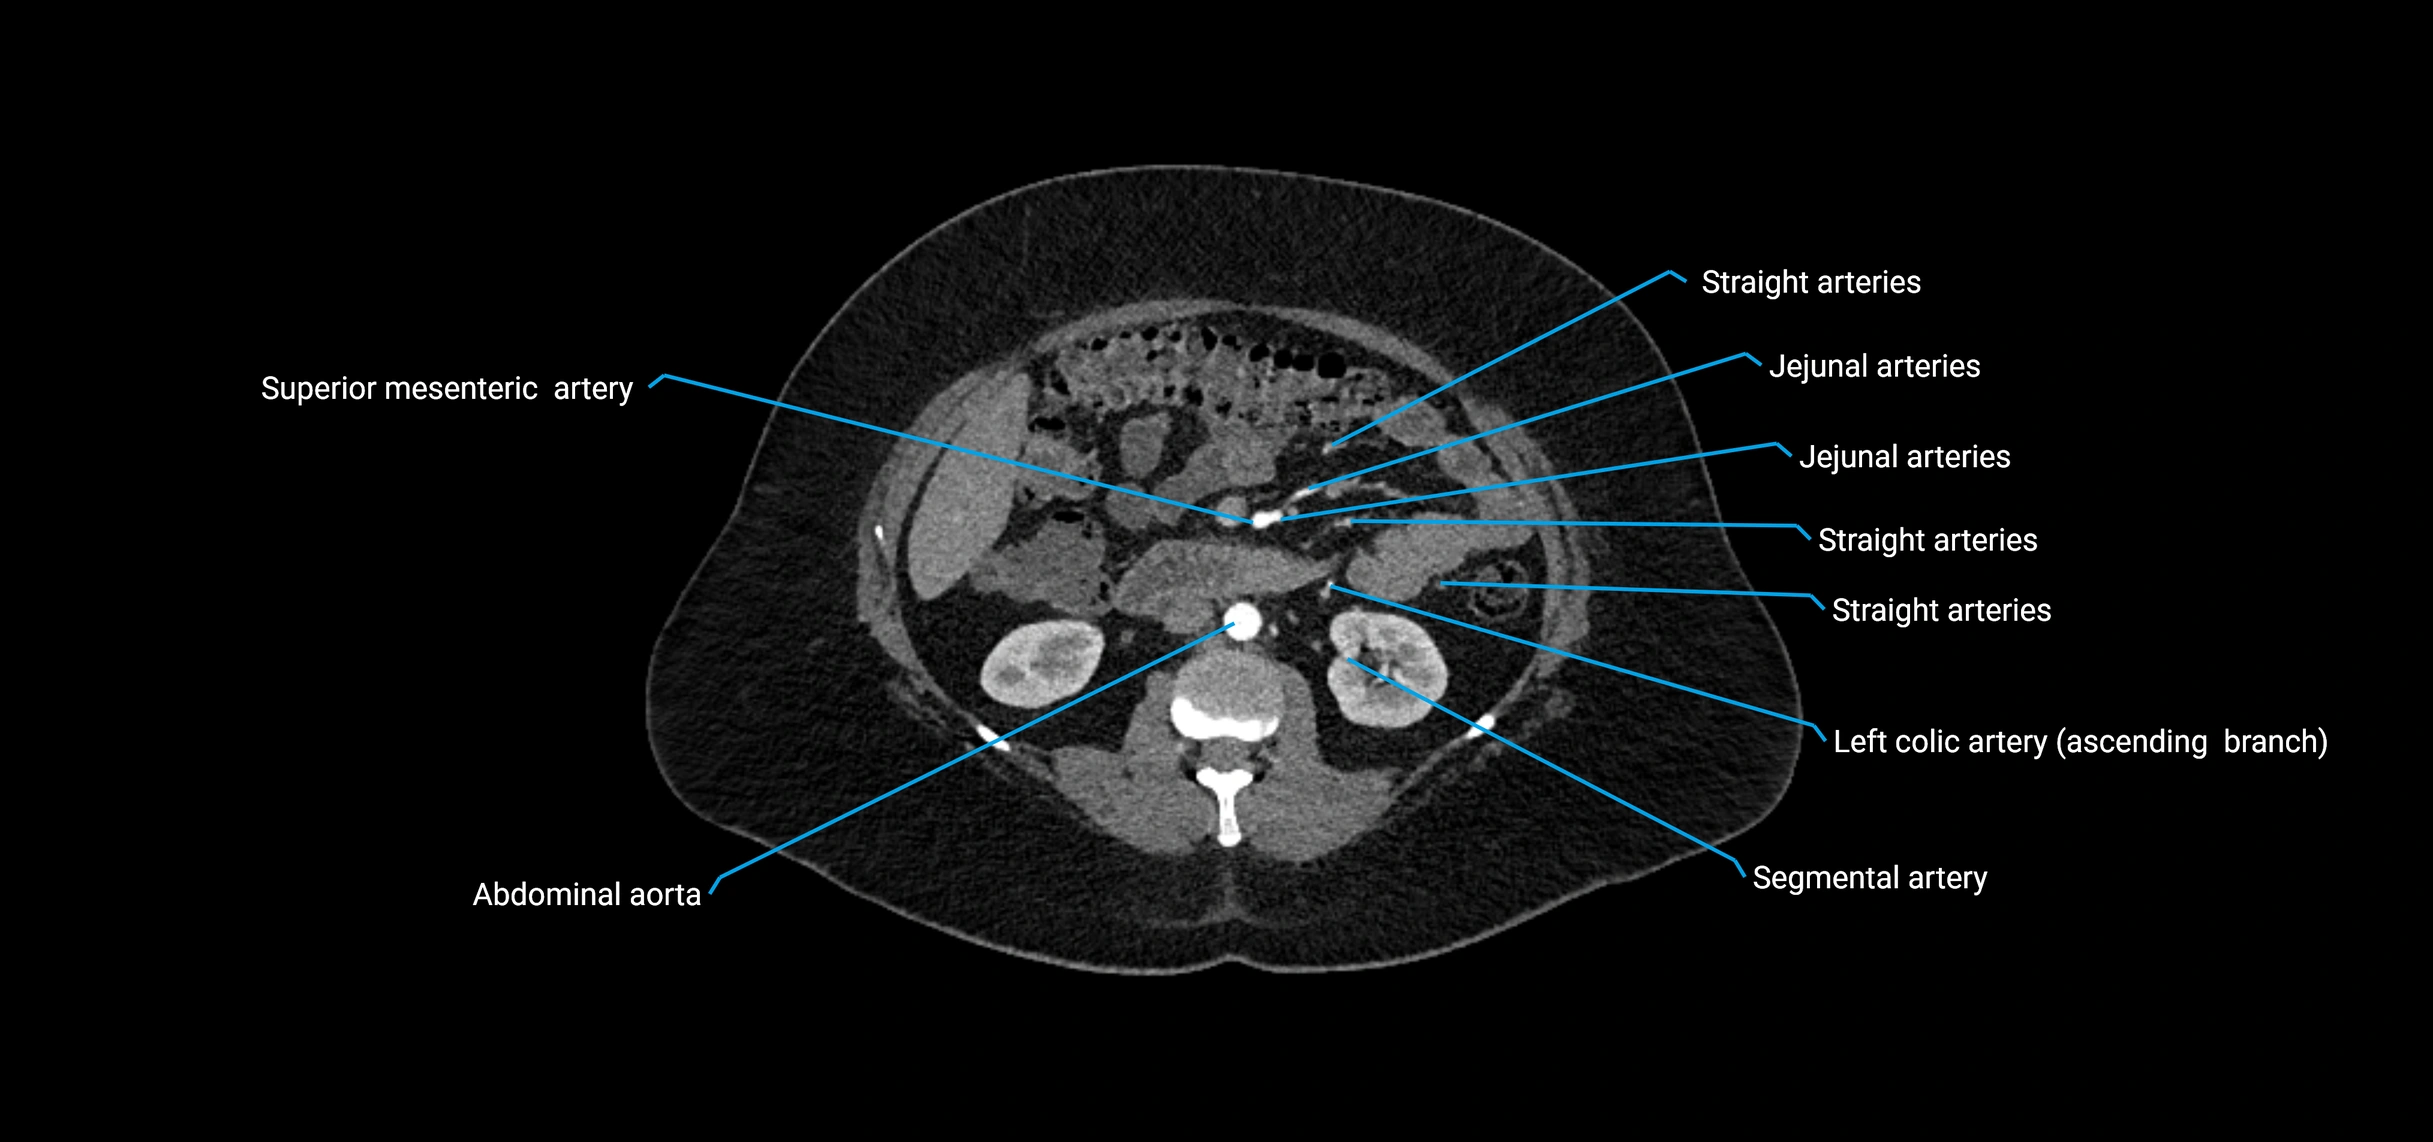

Contrast-enhanced CT (CTA):

• Gold standard for abdominal aortic imaging

• Provides excellent detail of lumen, wall, aneurysm, thrombus, and branch vessels

• Multiplanar and 3D reconstructions help in aneurysm measurement, stent graft planning, and dissection evaluation

• Detects acute rupture, traumatic injury, or occlusion with high sensitivity